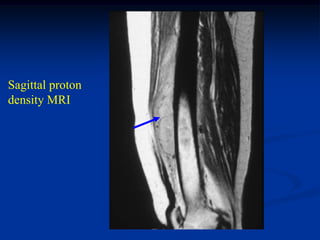

Case #261

62 year female

MFH anterior thigh

AP x-ray

Sagittal proton

density MRI

Sagittal T-2 MRI

Axial proton density MRI

Axial T-2 MRI